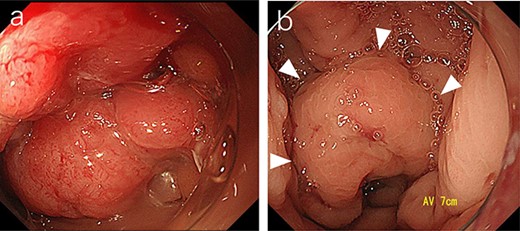

A 53-year-old Japanese man was admitted to the hospital with a chief complaint of buttock pain that lasted for 5 months and a recent weight loss of 8 kg, from 68 kg to 60 kg. He had no remarkable medical history. Digital rectal examination could not be performed because of severe pain. Laboratory findings revealed severe inflammation, indicated by an increased white blood cell count (16 790 cells/μL) and C-reactive protein (12.15 mg/dL). He was also undernourished with an albumin level of 2.7 g/dL. Tumor marker levels of carcinoembryonic antigen and cancer antigen 19–9 were within the normal ranges. Pelvic computed tomography (CT) showed contrast-enhanced thickening of the upper rectal wall and perirectal abscess (Fig. 1). Swollen lymph nodes were observed near the mesentery, but distant metastases were not detected. Rectal cancer accompanied by a pelvic abscess was then suspected. For the patient’s relief, sigmoid colonoscopy was performed under lumbar spinal anesthesia, which revealed a semicircular type 2 tumor in the upper rectum (Fig. 2a), and exclusion from outside the rectal wall on the anal side of the tumor at 7 cm from the anal verge (Fig. 2b). The colonoscope could not pass through the oral side of the tumor.

Sigmoid colonoscopy revealed a circular tumor in the upper rectum (a). Extramural compression due to an abscess is observed on the anal canal side of the tumor (arrowheads); however, the penetrated portion could not be detected (b).